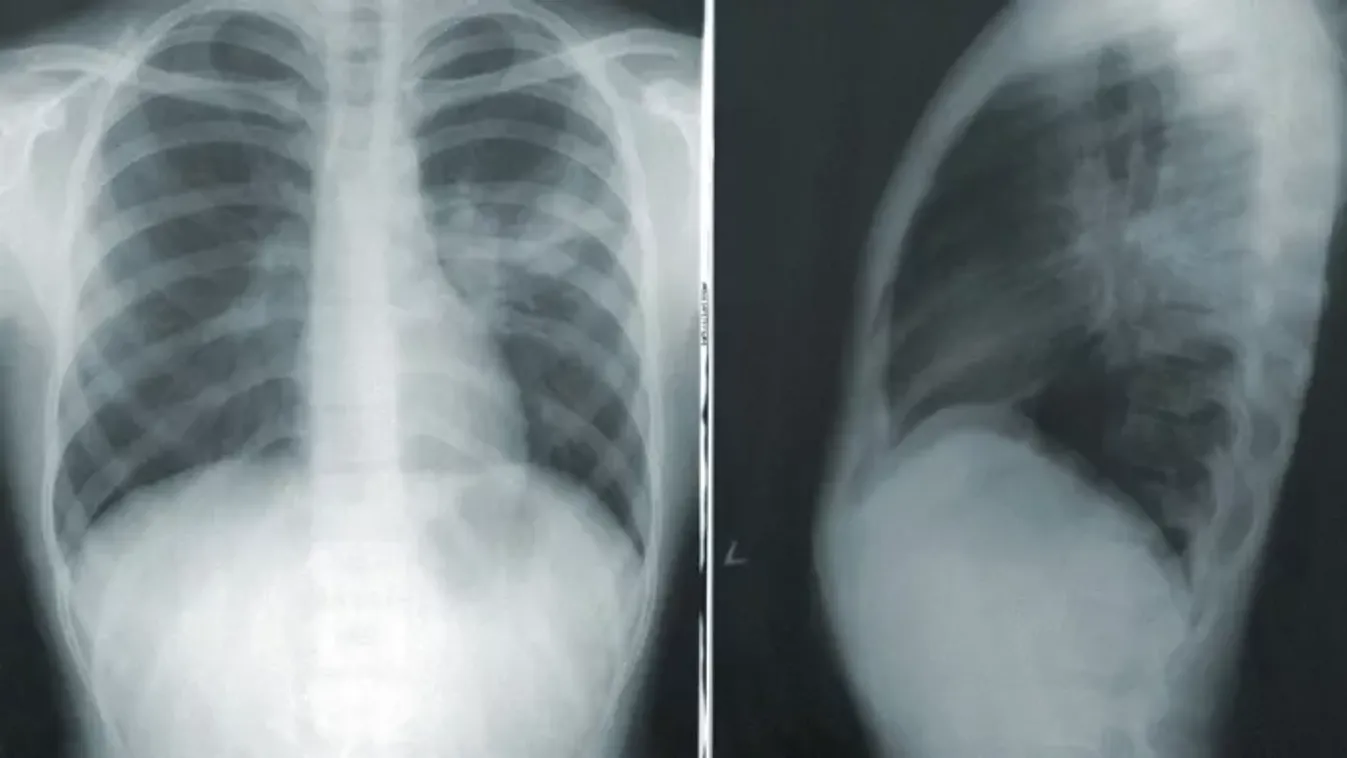

Az anyai megérzés ezúttal sem csalt: 15 alkalommal legyintettek az orvosok a baba panaszaira, majd kiderült a baj

A kisbaba többször is rosszul lett.